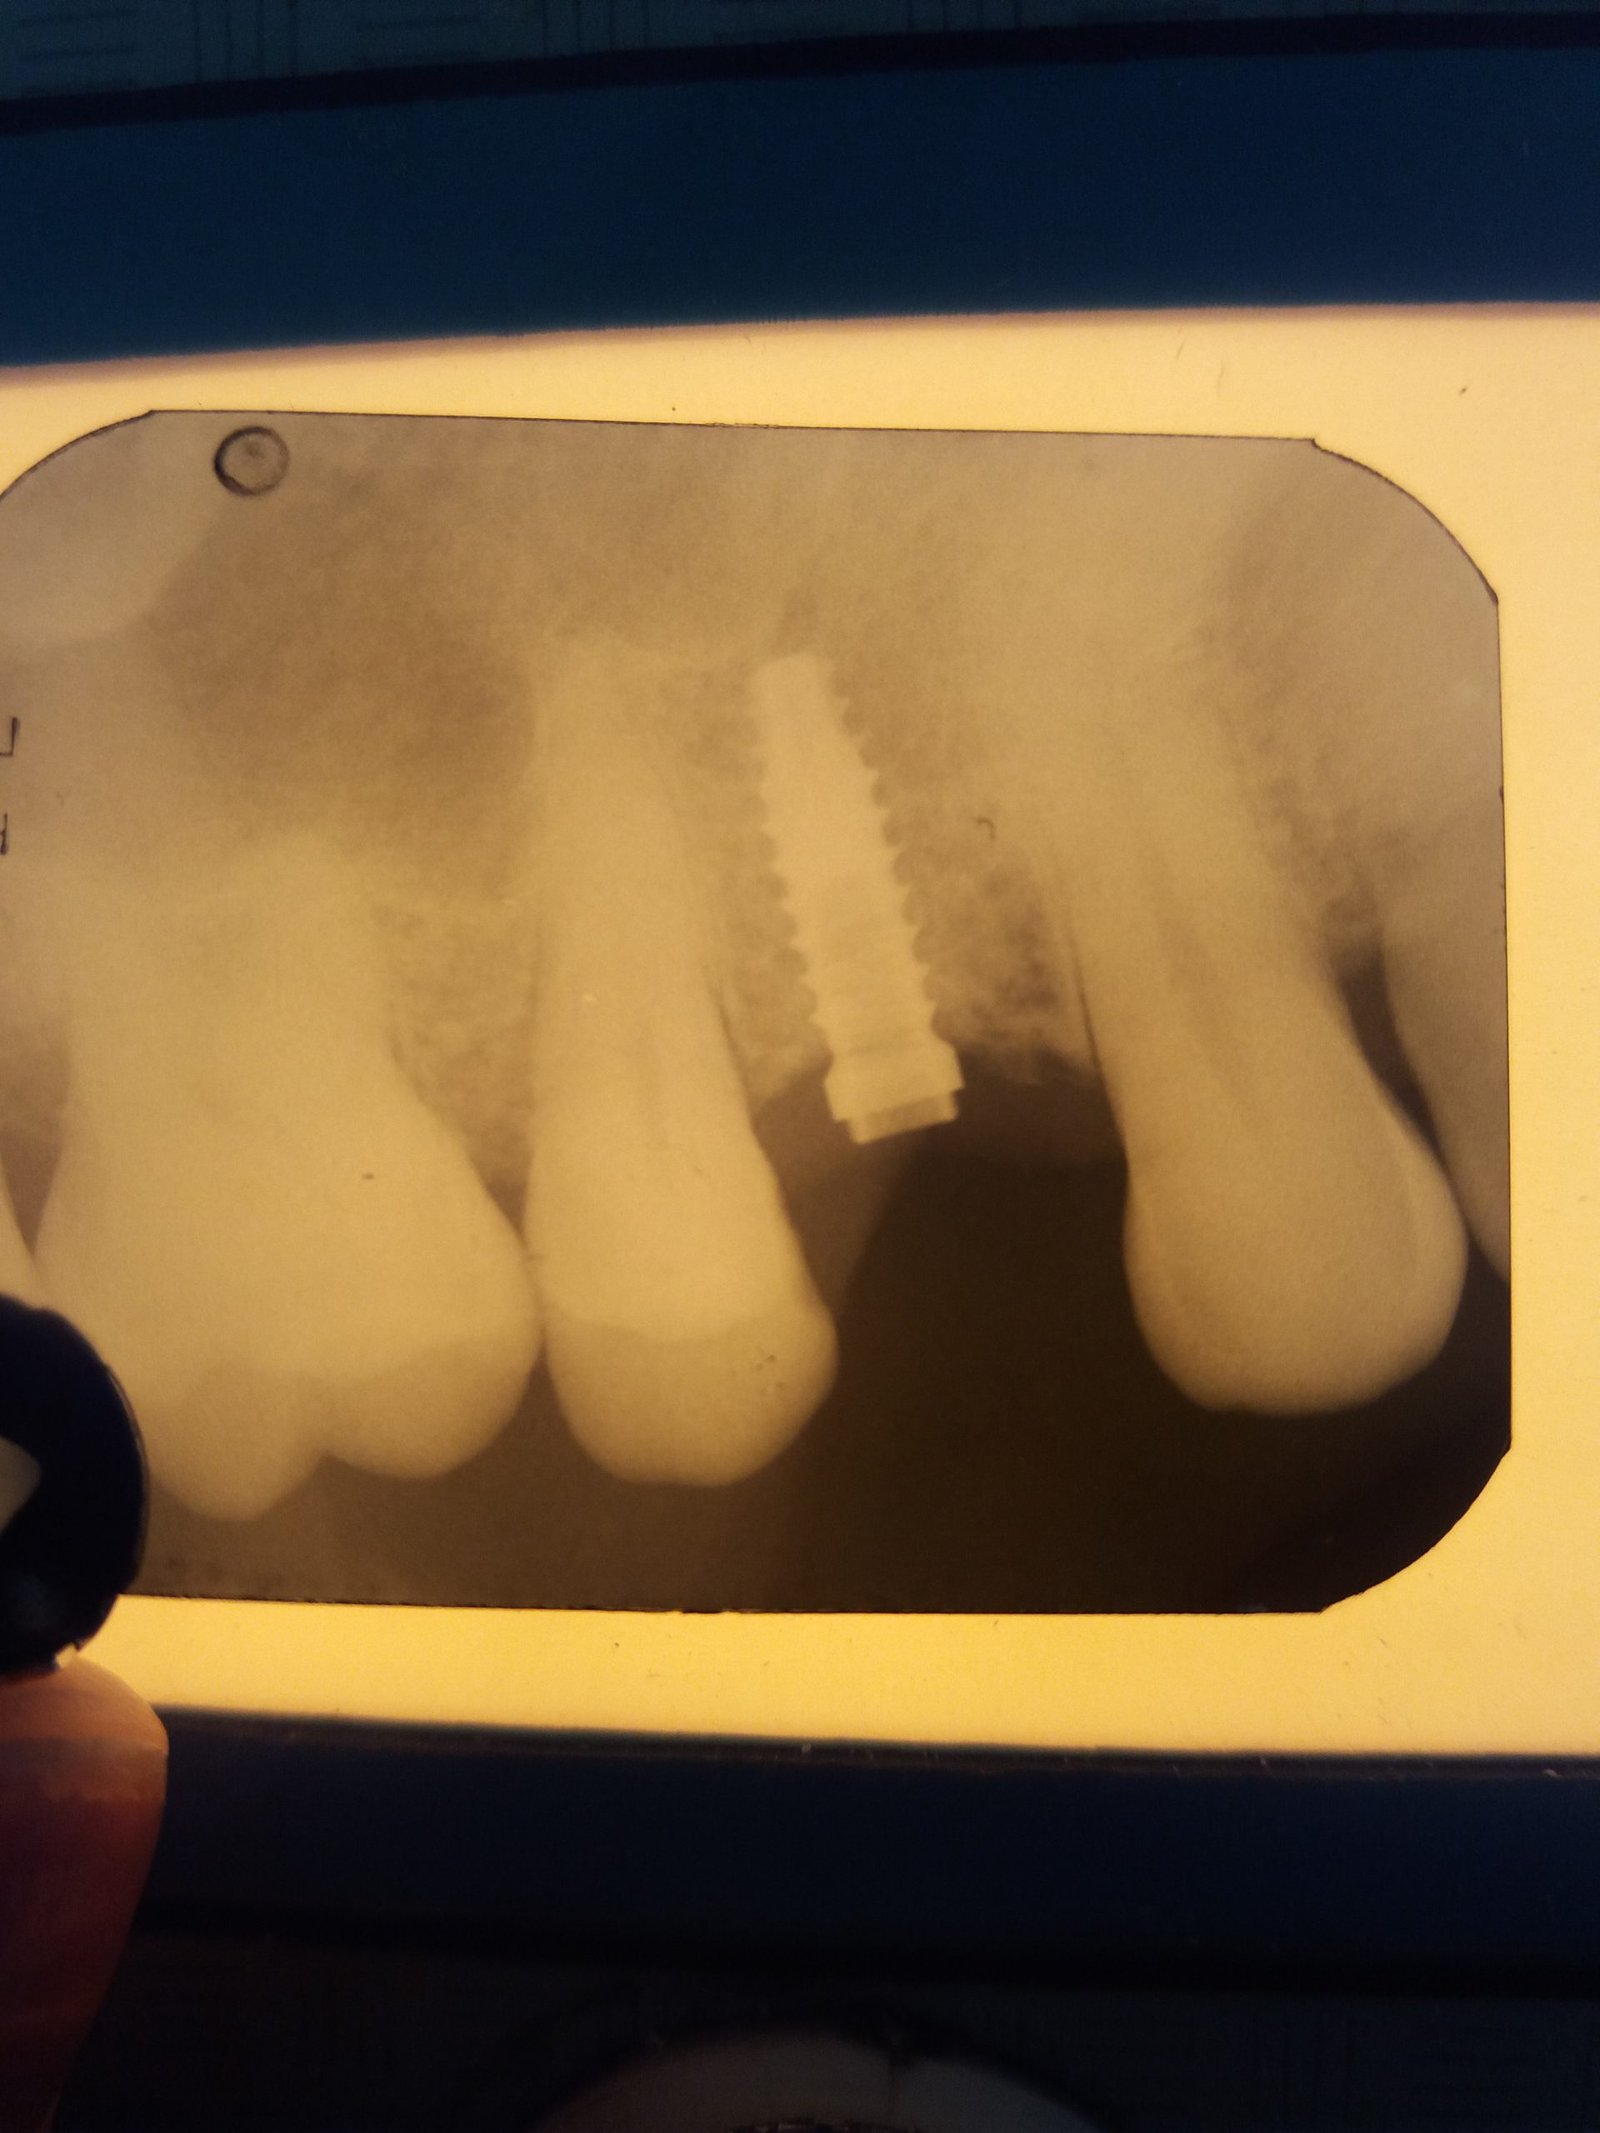

Me ayudan para saber que implante y medida es? Gracias